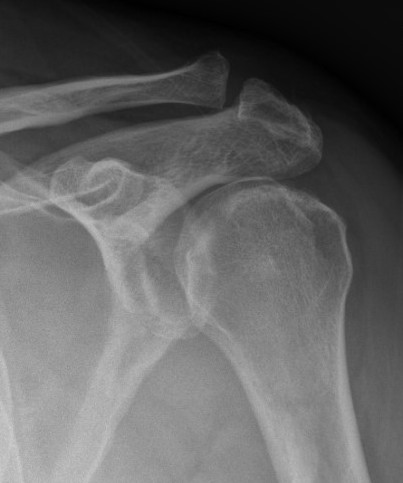

Type IA: Anterior glenoid rim fracture

Xray / CT